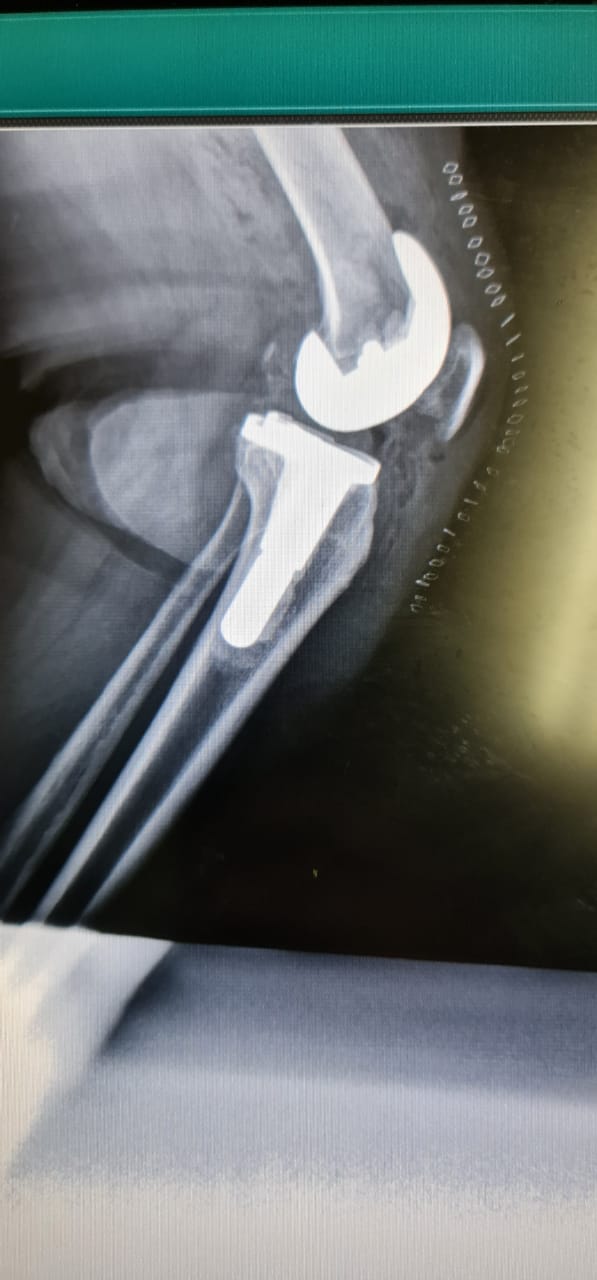

حيث تم إجراء عملية معقدة بقيادة استشاري جراحة العظام واستبدال المفاصل والطب الرياضي والمناظير الدكتور/ يوسف بن توفيق خوجة لإستبدال مفصل الركبة بالمفصل الصناعي تحت تخدير نصفي ، و وعي كامل للمريضة وتكللت العملية بالنجاح وبدون حدوث مضاعفات ، حيث تمكنت المريضة من المشي بعد العملية بساعتين وخروجها من المستشفى بعد يومين من إجراء العملية وهي في حالة مستقرة ولله الحمد.